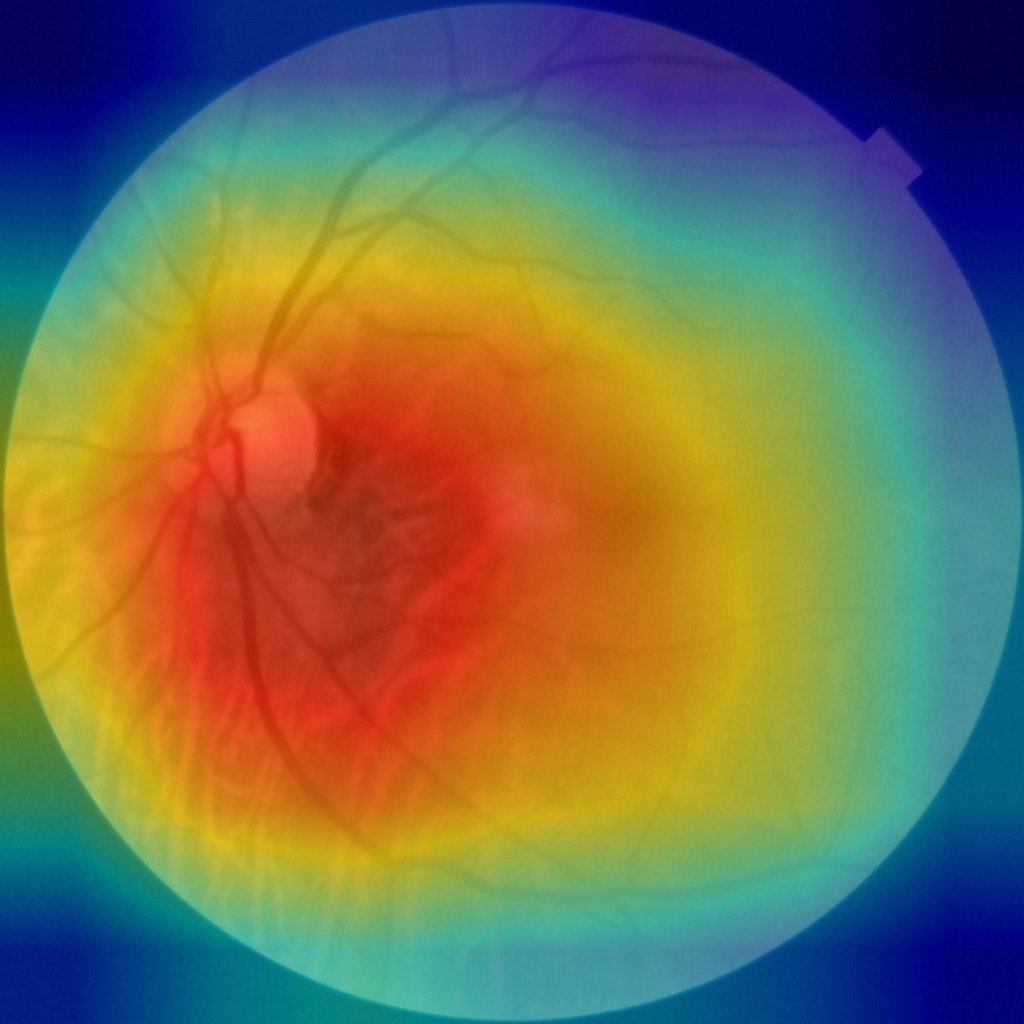

4.4 注意力热力图对比

使用Grad-CAM生成病灶区域可视化:

以数据集中0001(NFMK1).jpg为例

原图像如下:

训练预处理后图像:

注意力热力图: